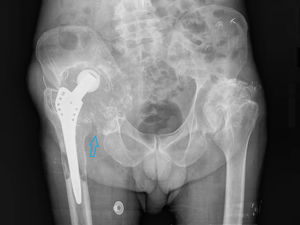

Presentamos el caso de un paciente de 66 años, recientemente diagnosticado de carcinoma vesical tras estudio de hematuria, que presenta cuadro de cojera y masa inguinal derecha indolora, de consistencia dura a la palpación. Como antecedentes personales destaca una artroplastia total de cadera derecha hace años por artrosis severa. La radiografía AP de cadera bilateral mostraba una importante destrucción ósea de la articulación coxofemoral derecha (fig. 1). Ante dichos hallazgos, se realizó PET/TC con 18F-FDG como estudio de extensión de proceso neoformativo primario vesical, con posibilidad de afectación metastásica ósea. En las imágenes a los 60min postinyección de la 18F-FDG se evidenció una gran masa de partes blandas multilobulada hipermetabólica en la región ilíaca derecha, que englobaba el material protésico y producía lisis de la pala ilíaca, con importante destrucción de la articulación coxofemoral (fig. 2). Se procedió a realizar biopsia ante los hallazgos indicativos de malignidad, con resultado de enfermedad de partículas por desgaste de los componentes de artroplastia. El paciente desestimó la posibilidad de revisión quirúrgica y se encuentra actualmente en seguimiento periódico.